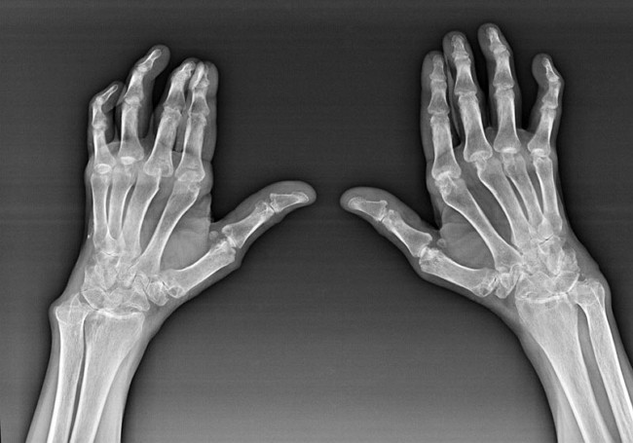

Rheumatoid arthritis

Rheumatoid arthritis is a disease in which the human immune system damages their own body tissues.In other words, rheumatoid arthritis is an autoimmune pathology.This disease is also systemic because many tissues are affected with it (Muscles, joints, vessels, etc.) and organs (Heart, kidneys, lungs, etc.) in the body.

Despite the fact that rheumatoid arthritis is a systemic disease, to a greater extent are the joints, while the lesion of other tissues and bodies in the background.With this disease, almost all types of brush compounds can be affected (Hand walls, carpal trails, metacarpal-phalanx, inter-phalan wrists).Lesia is usually symmetrical (They.The same compounds are affected) On both hands, accompanied by swelling, pain in damaged joints.In the morning, during the bed of bed there is some stiffness in affected joints, which can last about 1 hour and then disappear without a trace.

Often often with rheumatic arthritis near affected brush joints (More often piano-falanx, inter-falan wrists) Rheumatoid nodes appear.They are a rounded formation located under the skin.On the brushes, these formations most often appear on the back.In palpation are thick, inactive, painless.The number of them can vary.